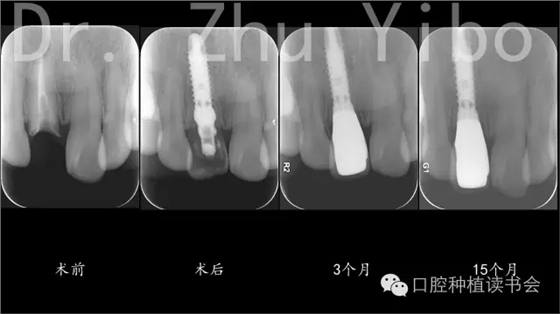

口腔種植讀書會(huì)是由國(guó)內(nèi)著名院校的中青年學(xué)者發(fā)起成立的公益性學(xué)術(shù)組織。“公益、分享、進(jìn)步”是口腔種植讀書會(huì)成立的愿景,通過(guò)對(duì)國(guó)際權(quán)威口腔種植學(xué)著作及文獻(xiàn)的出版與推廣,結(jié)合臨床案例與科研進(jìn)展,秉承“嚴(yán)謹(jǐn)、求實(shí)、循證”的理念為口腔醫(yī)生與技師奉獻(xiàn)最新、最實(shí)用的的口腔種植知識(shí)與技術(shù),并定期推出學(xué)術(shù)著作及線上、線下公益課程,推動(dòng)口腔種植事業(yè)更好的發(fā)展。 上頜前牙區(qū)即刻種植治療極具挑戰(zhàn)性。一方面由于患者對(duì)于種植美學(xué)求很高,一方面由于上頜前牙區(qū)通常牙槽骨較薄,牙齦菲薄,拔牙后牙槽骨、牙齦極易發(fā)生吸收、退縮,影響種植修復(fù)的美學(xué)效果。目前為止,國(guó)內(nèi)、外還沒(méi)有一種可靠的技術(shù)能夠確保上頜前牙區(qū)即刻種植的長(zhǎng)期美學(xué)效果。本報(bào)告的患者為29歲女性。主因“右上前牙牙冠脫落1日”來(lái)院就診。患者2年前于外院行右上前牙樁核冠修復(fù),1日前進(jìn)食時(shí)修復(fù)體脫落,來(lái)院咨詢治療案。臨床檢查見:11殘根,松(-),齦(-),斷面齲壞,平齊牙齦齦,牙齦菲薄。21外翻(圖1)。術(shù)前根尖片及CBCT示:11根尖區(qū)低密度影,牙根腭側(cè)有橫向裂紋,唇側(cè)骨板薄,牙槽突與牙根長(zhǎng)軸基本一致,符合一型分類(圖12、13)患者因時(shí)間、費(fèi)用問(wèn)題,拒絕正畸治療,強(qiáng)烈要求即刻種植、即刻修復(fù)。

5、術(shù)后拍根尖片,確認(rèn)臨時(shí)冠就位良好(圖12)。

8、戴最終修復(fù)體,就位良好(圖12)。 術(shù)后1年復(fù)查,牙冠完好,牙齦美學(xué)評(píng)分14分(圖10、11)。